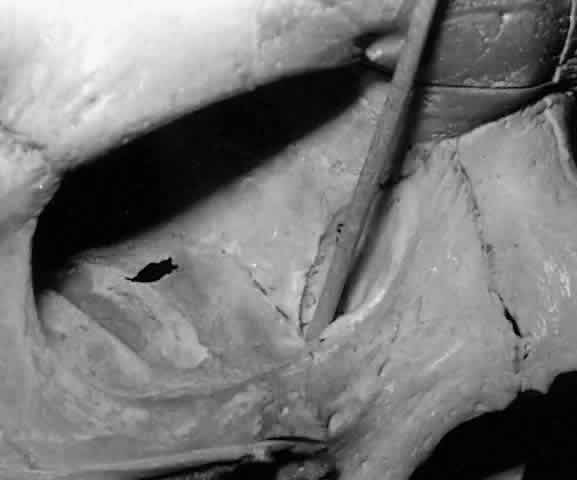

In some cases, the nasolacrimal duct may empty directly into the roof of the inferior meatus, but in the majority, the opening is on the side wall of the inferior meatus (Fig. 22), 30 mm behind the lateral margin of the anterior nares. In children and infants, the opening is found 20 mm behind the lateral margin of the anterior nares. In a small number of cases, the nasolacrimal duct is found to course beneath the mucosa of the lateral nasal wall without opening into the nose.24,25

Fig. 22. A twig placed in the right nasolacrimal fossa of this skull is seen exiting below the inferior turbinate (arrow 1). The middle turbinate (arrow 2) is seen lying medial to the nasolacrimal fossa (arrow 3).